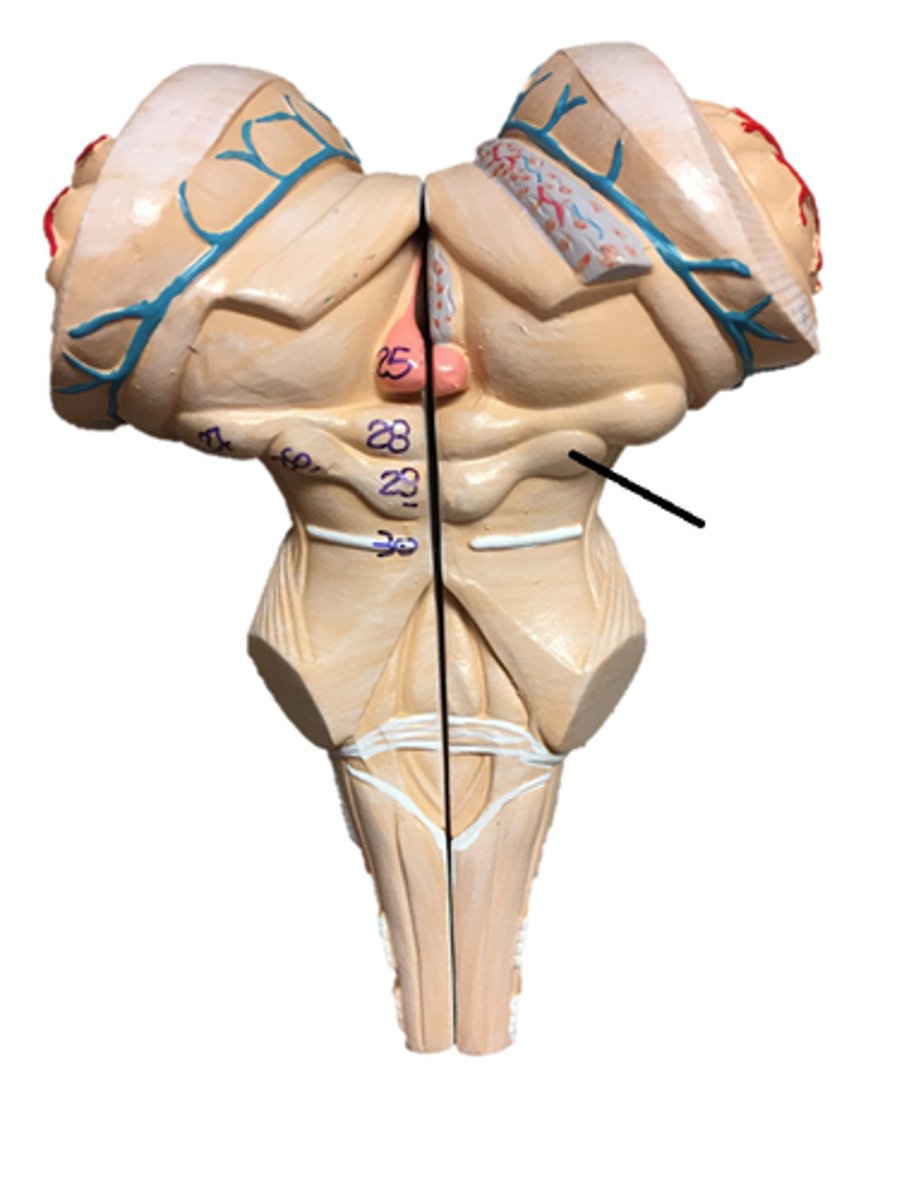

pons

midbrain

medulla oblongata

olive

superior colliculi

inferior colliculi

cerebral peduncles

vermis

cerebellar peduncles